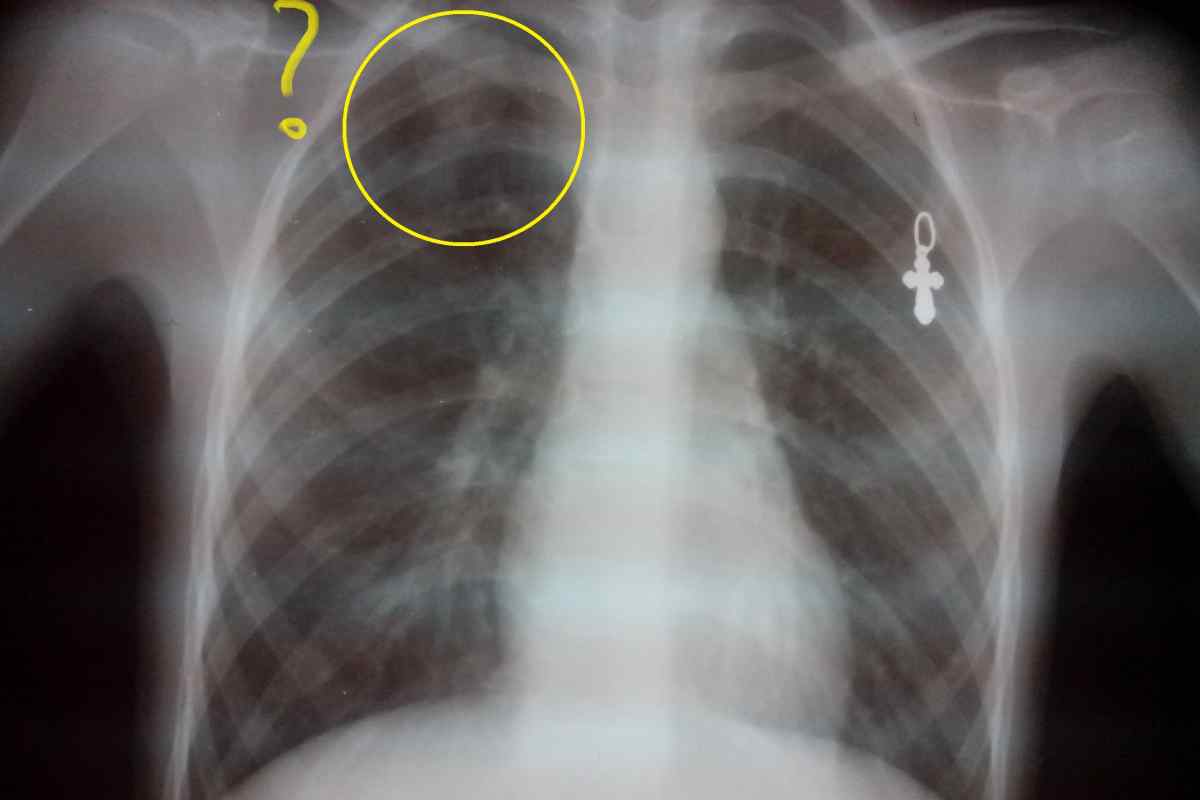

Рентген здоровых легких: примеры снимков и советы

Раздел: Сокровищница опыта